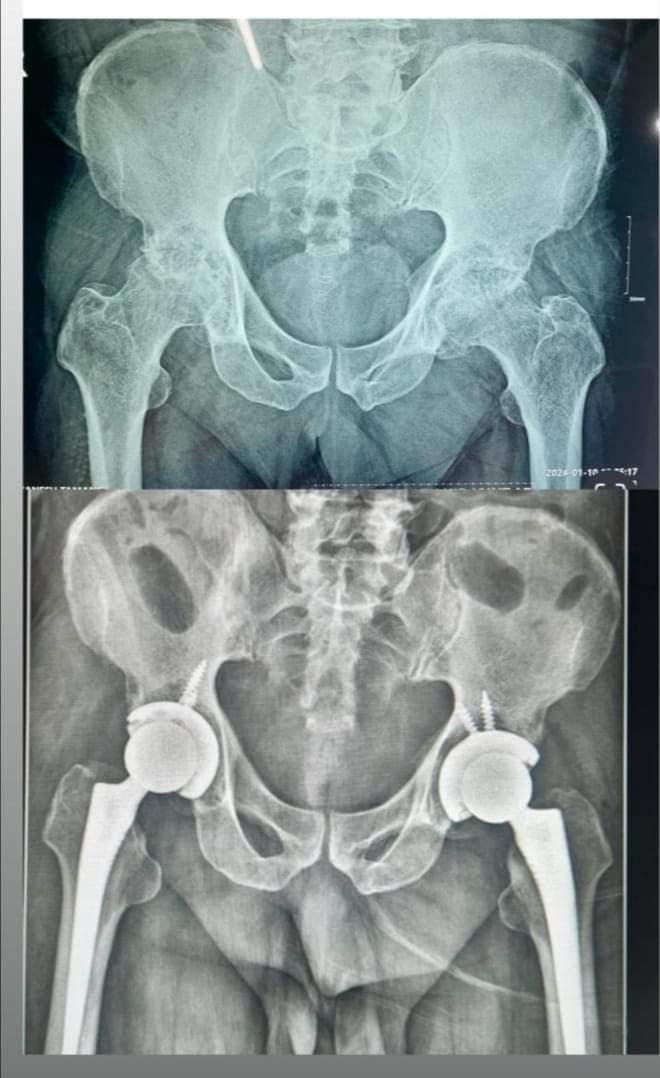

गान्तोक: जिल्ला अस्पताल नाम्चीको अर्थोपेडिक विभागले ७७ वर्षीय वृद्धको हिप जोइन्टको सफलतापूर्वक बाई लेटरल टोटल हिप रिप्लेसमेन्ट गरेको छ। वृद्ध विगत ५ वर्षदेखि बिराम थिए। बिमारीको कारण उनलाई हिड्न गाह्रो भइरहेको थियो।

उल्लेखनाय छ, जिल्ला अस्पताल नाम्चीले केही वर्षदेखि सबै प्रकारका आर्थ्रोप्लास्टिक शल्यक्रियाहरू (कुल हिप रिप्लेसमेन्ट, कुल घुँडा प्रतिस्थापन, काँध प्रतिस्थापन र कुहिनो प्रतिस्थापन) सञ्चालन गर्दै आएको छ। हड्डी शल्यक्रियाका लागि खाँचोमा परेकाले नाम्ची जिल्ला अस्पतालमा आउन सक्ने अस्पताल सञ्चालन पक्षले सर्वसाधरणलाई अपील गरेको छ।